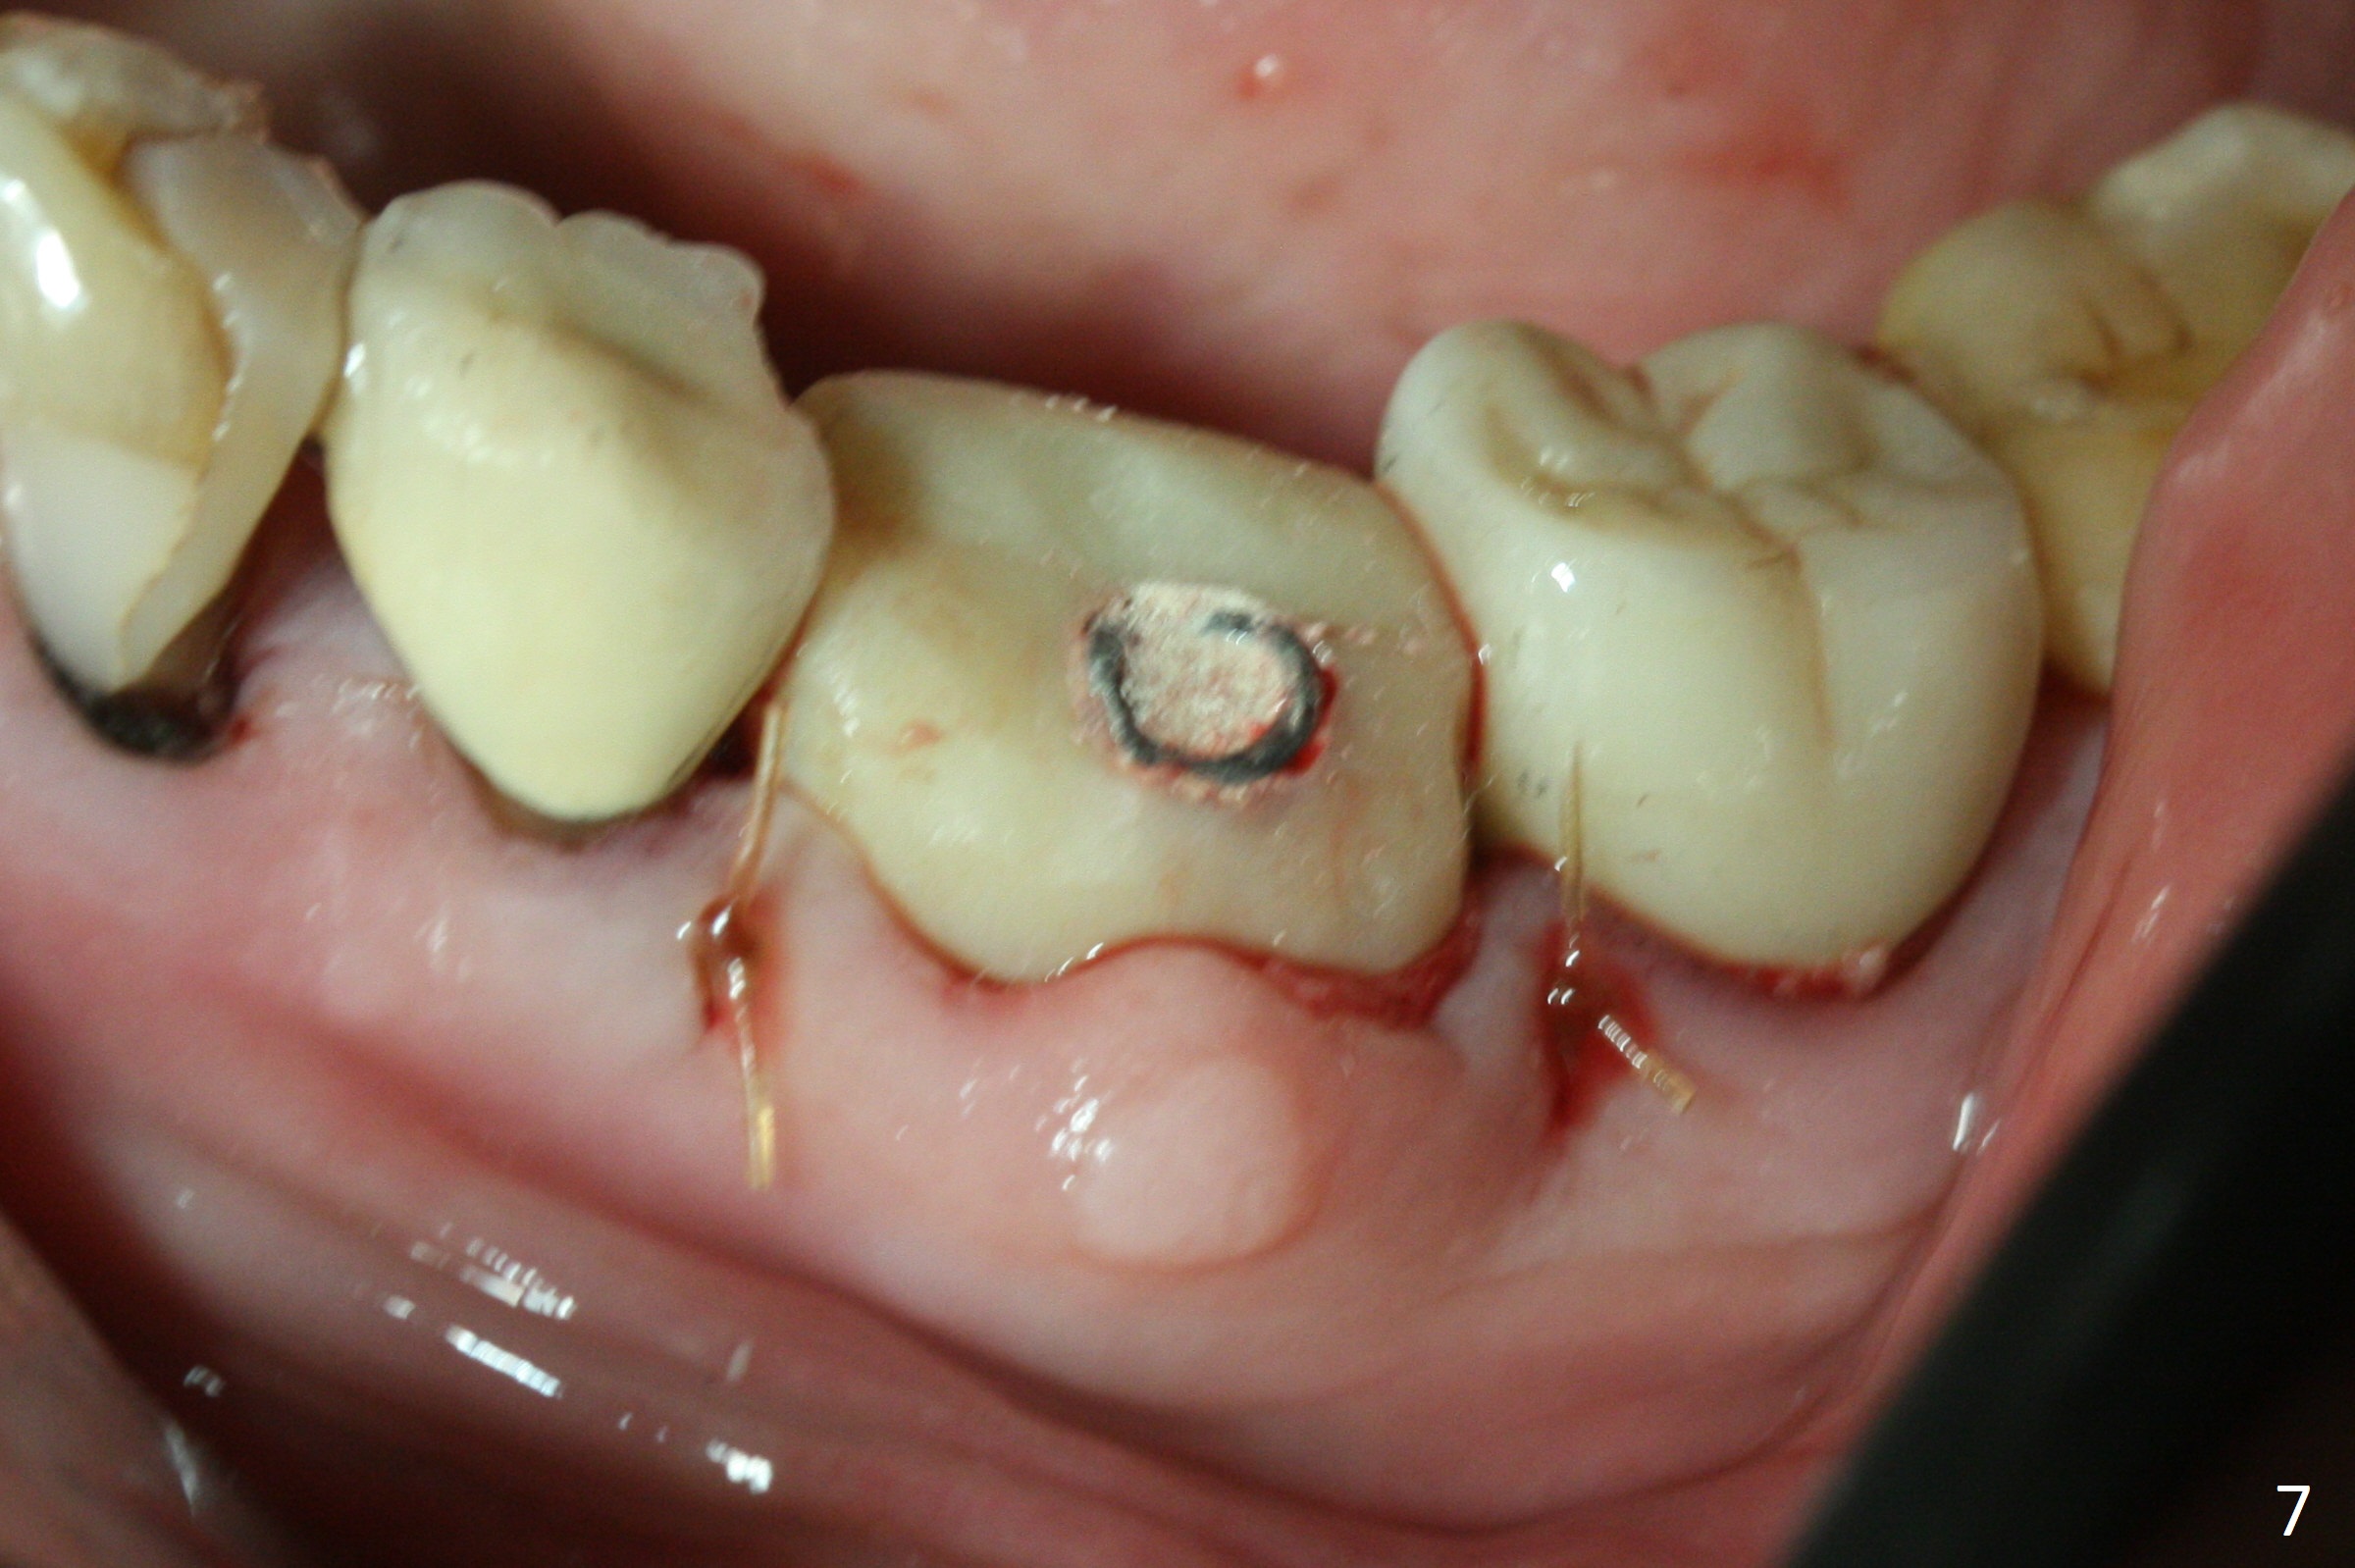

Extraction of the residual roots at #19 (Fig.1) is difficult, partially due to the hard one. The latter contributes to primary stability of 5x10 mm IS implant placed in the septum (Fig.2 (*),3). After change of cementation abutment (5.2x4.5(2) mm (short for provisional)) to hexed temporary abutment (5.2x8(2) mm), Collagen plug and Vera Graft are placed in the remaining mesial and distal socket (Fig.4 *). The last PA is taken when the temporary abutment (Fig.6 (<: hexed portion)) and provisional (P) are removed for modification. Before the abutment/provisional complex returns, a 2nd round of graft is placed (Fig.5 *). After the complex is seated, a 3rd round of graft is placed buccally (Fig.7). The temporary abutment is retightened 2 months postop (Fig.8). The implant appears to be osteointegrated 3.5 months postop (Fig.9). The gingiva looks healthy with (Fig.10) and without the provisional (Fig.11,12). It appears that there is no or minimal buccal plate loss. After insertion of a 5.7 x3 mm 15 degree (B-type) angled abutment (Fig.13) and height adjustment, impression is taken. The provisional is reseated after impression. The mesial bony defect seems to have been repaired nearly 8 months postop, 3 months post cementation (Fig.14 *). The bone density increases mesially 11 months post cementation (Fig.15).